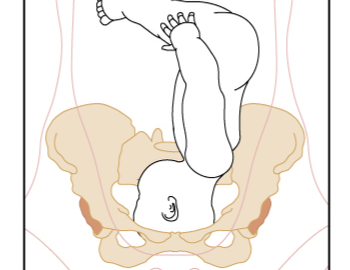

A growth scan is a routine obstetric ultrasound scan performed for expecting mothers in the third trimester.